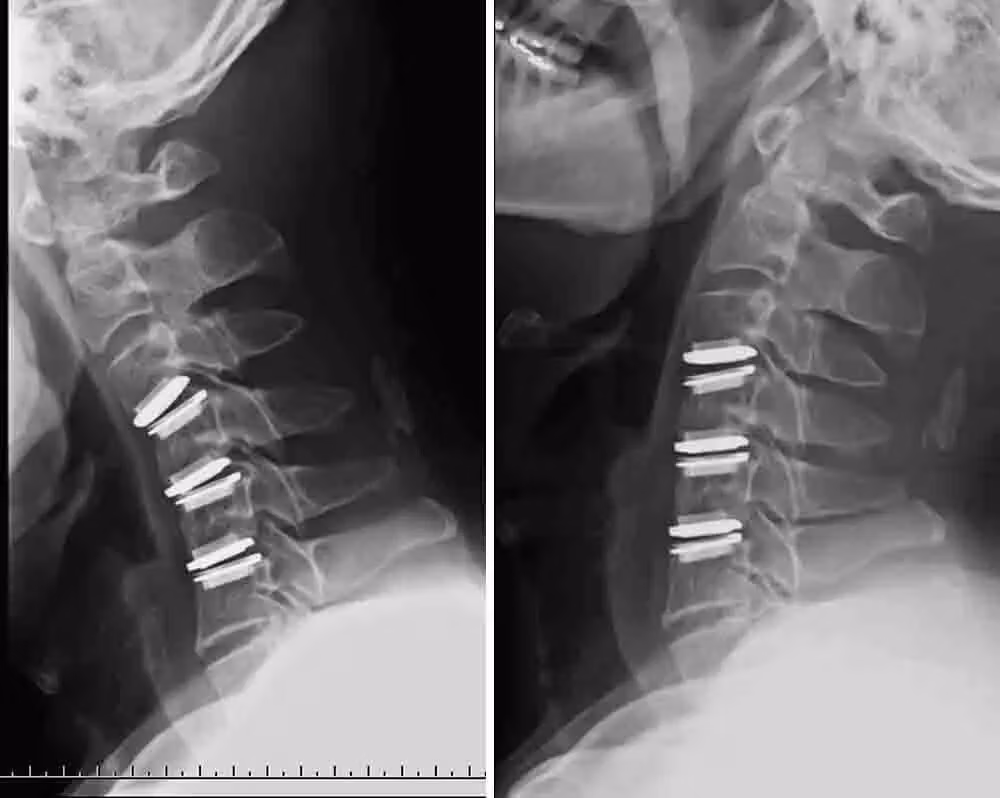

تعویض دیسک مصنوعی (آرتروپلاستی دیسک بینمهرهای) یا تعویض کامل دیسک (آرتروپلاستی ستون فقرات)، نوعی جراحی ستون فقرات است که طی آن دیسک آسیبدیده با یک مفصل مصنوعی جایگزین میشود. در این عمل، جراح ستون فقرات، دیسک مشکلدار را خارج کرده و یک پروتز فلزی یا پلاستیکی را میان مهرهها قرار میدهد.

زمانی که دیسک فرسوده از ستون فقرات خارج میشود، صفحههای بالایی و پایینی دیسک مصنوعی به مهره متصل خواهند شد. پس از جایگذاری این صفحات، بخش مرکزی (هسته) که اصطلاحاً core نامیده میشود میان آنها قرار میگیرد. این هسته مرکزی امکان خم شدن و انعطاف را در ستون فقرات فراهم میکند تا حرکت ستون فقرات مشابه حالت طبیعی باقی بماند.

۱. تعویض دیسک گردنی

در این روش، جراح برشی به طول سه تا چهار سانتیمتر در بخش جلویی گردن ایجاد میکند تا به مهرههای گردنی دسترسی داشته باشد. سپس دیسک آسیبدیده را بیرون میآورد و سطح مهرهها را صاف میکند. صفحههای فلزی به مهرهها متصل و پیچ میشوند. در نهایت، یک هسته پلیمر بین این صفحات قرار داده میشود تا نقش دیسک را ایفا کند. در پایان، این صفحات فلزی به مهرهها جوش میخورند.

از جمله دیسکهای مصنوعی متداول در این روش میتوان به Prodisc-C، Mobi-C، Medtronic Prestige LP و M6-C اشاره کرد.